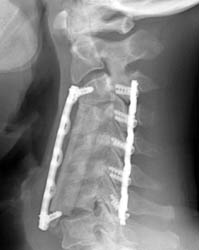

Lateral radiograph 4 months post-op demonstrating the strut graft now

displaced

anteriorly, and the

inferior fixation screw is not located in the vertebral body. No acute fracture

seen.